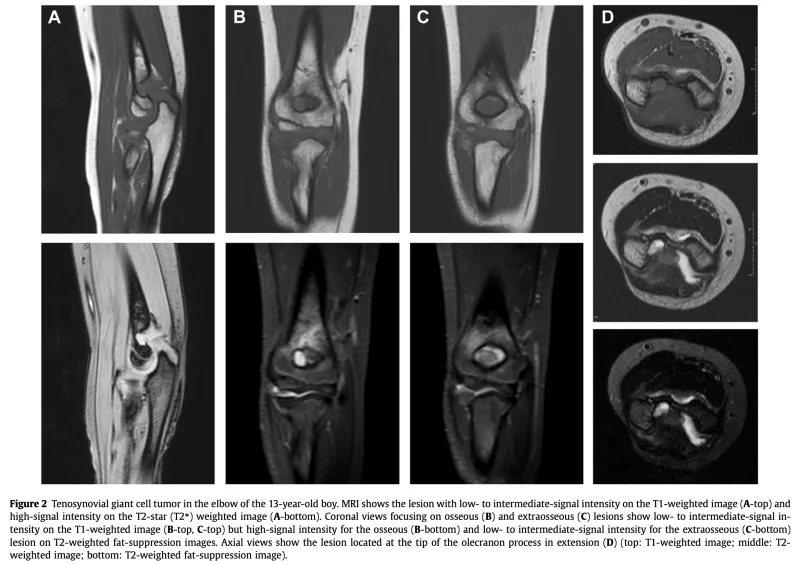

抗CCP抗体が高値だったため関節リウマチが疑われましたが, MRIの結果, 滑膜の腫瘍(びまん型腱滑膜巨細胞腫)の可能性も示唆され, 当院での生検を勧められて来院されました.

この腫瘍は, かつて『色素性絨毛結節性滑膜炎(PVNS)』と呼ばれていた疾患で, 現在は滑膜由来の良性腫瘍に分類されています.

中高年女性の膝関節や股関節に多く発生しますが, 肘関節に生じるのはまれです.